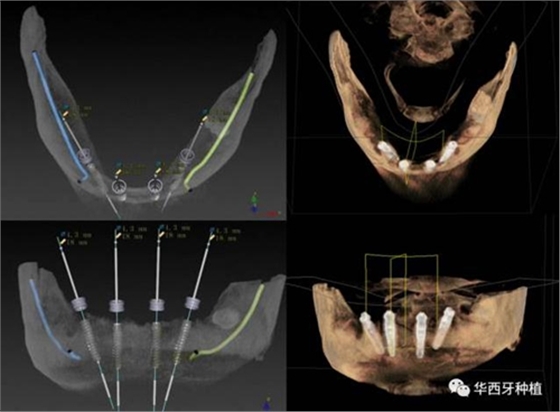

吳教授提到了使用數(shù)字化建模與導板的聯(lián)合應(yīng)用,不僅可以從設(shè)計上降低修復(fù)難度,便于在修復(fù)為導向的設(shè)計中種植體方向的確定,同時可以加入微創(chuàng)的手術(shù)方法,減輕術(shù)中創(chuàng)傷。

對于傳統(tǒng)的all-on-four術(shù)式,吳教授加入了微創(chuàng)的指導思想,設(shè)計時同樣加入數(shù)字化三維重建與修復(fù)一體化設(shè)計,增加了手術(shù)的可控性,同時極大減輕了患者的創(chuàng)傷程度,縮短了修復(fù)周期。